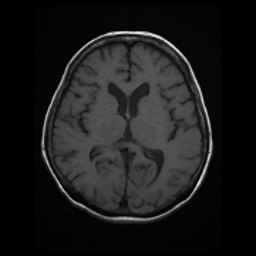

| 頭部T2強調画像 | 頭部T1強調画像 |